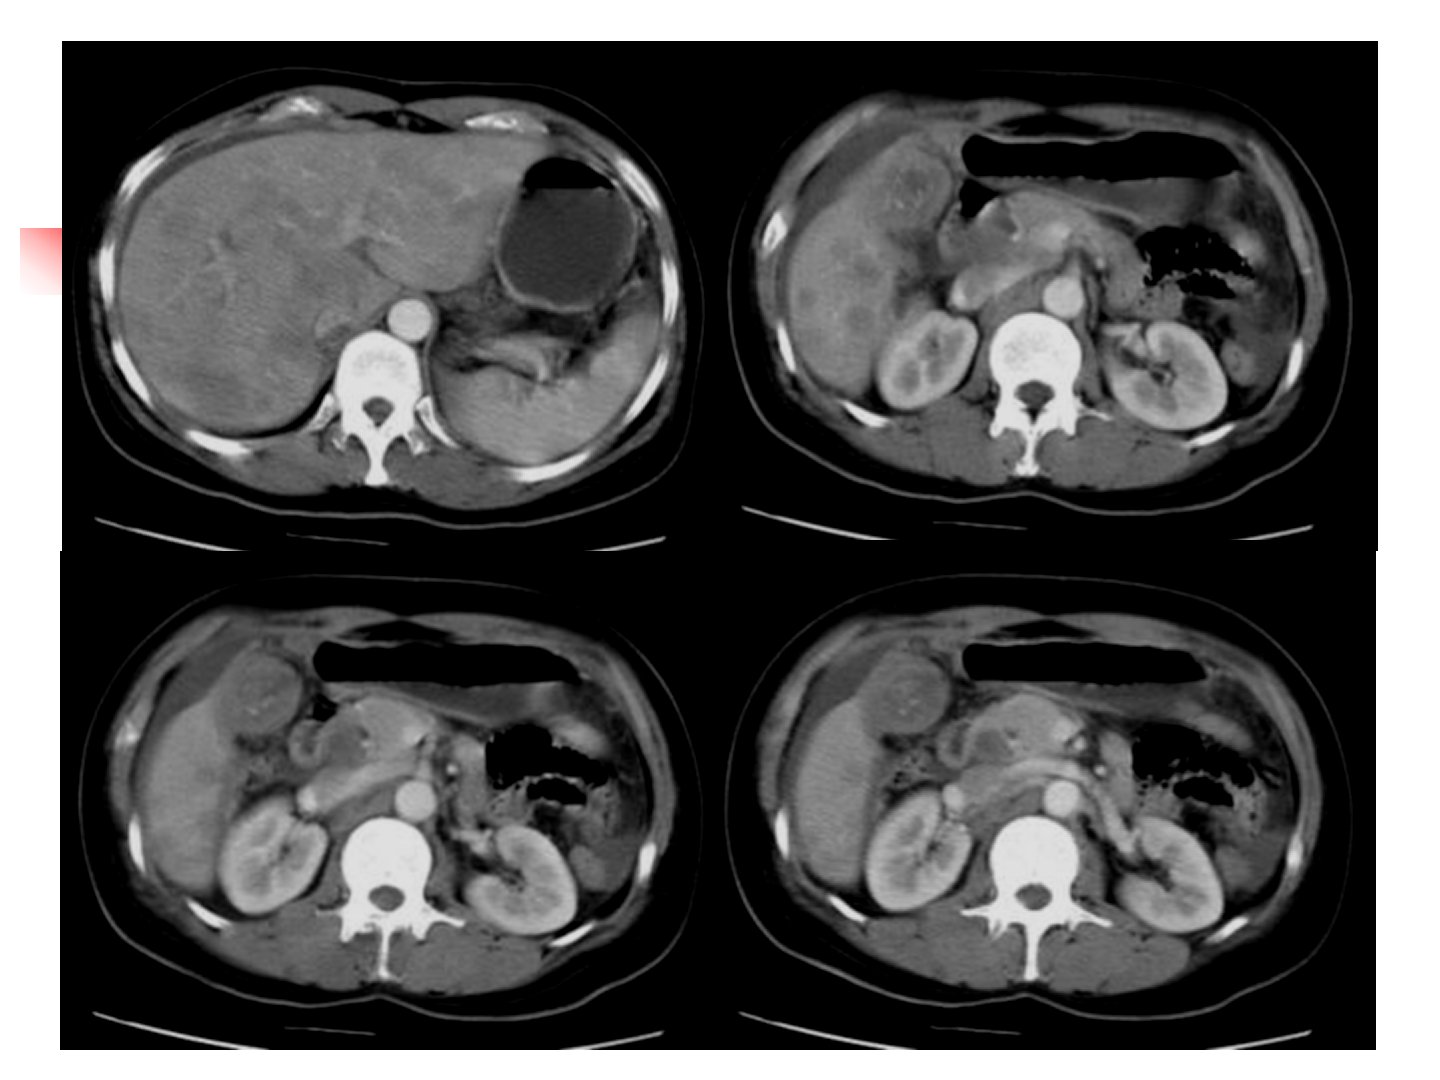

肾、盆腔、急腹症CT诊断摘要东南大学临床医学院对肾、盆腔、急腹症CT诊断展开研究。肾脏CT检查中平扫与增强各有特点正常肾脏CT解剖清晰。常见肾脏病CT诊断方面肾囊肿位于实质内单发或多发有明确诊断标准;多囊肾双侧发病呈蜂窝状;肾血管平滑肌脂肪瘤是常见良性肿瘤CT能显示脂肪密度;肾细胞癌起源于肾实质上皮细胞CT表现多样小肾癌易漏诊动脉扫描可提高诊断率;肾盂癌表现为肾盂肾盏内肿块。腹部外伤CT诊断无损伤肝、脾、肾外伤各有特征性CT表现。盆腔CT诊断中介绍了检查方法正常CT解剖包括男性前列腺、精囊及女性宫颈、子宫等。常见病变CT诊断有前列腺增生、前列腺癌、子宫肌瘤、卵巢癌、膀胱癌等CT对肿瘤分期、转移判断有重要价值。